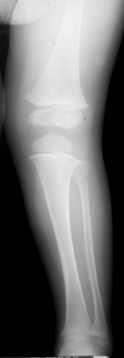

Teleskopnagelung in der Osteogenesis imperfecta-Behandlung

Bei der operativen Behandlung steht die Versorgung von Knochenbrüchen oder Achsfehlstellungen mit Teleskopnagelungen im Vordergrund. Aus orthopädischer Sicht ist trotz ständiger Bruchgefahr viel Bewegung wichtig, um eine stützende Muskulatur aufzubauen und Skelettveränderungen vorzubeugen bzw. zu verzögern.